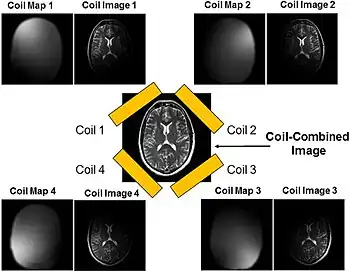

Parallel imaging

Parallel imaging coil collection

Parallel imaging involves the addition of multiple coils surrounding the target with each coil acquiring a fraction of the total image. Because modern GPUs have parallel processing capabilities, they can reconstruct each portion of the image simultaneously. Therefore, the more coils used, the faster the acquisition of the MR images.[15]